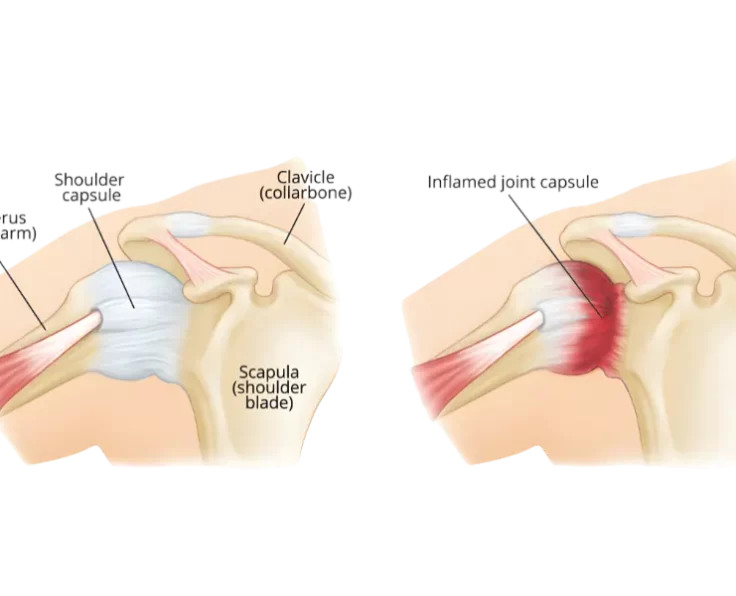

Capsule Release

The operation seeks to shorten healing time by allowing the joint to move freely and relieve pain.